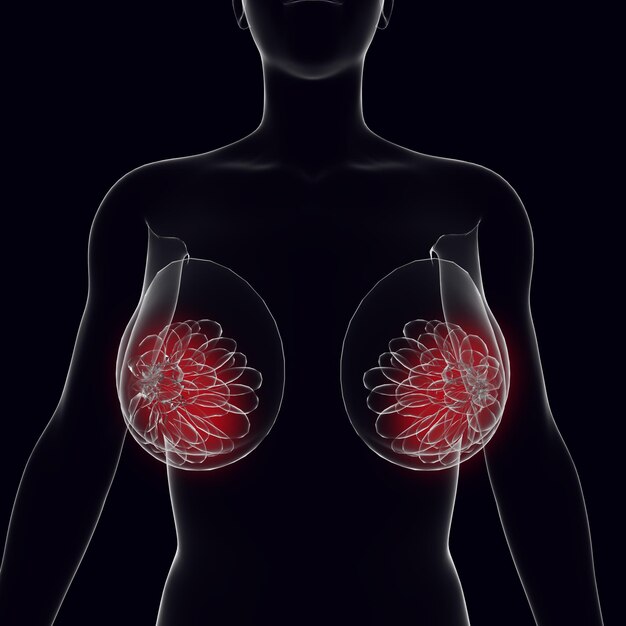

Breast cancer is the leading cancer among women globally, with over 2 million new cases diagnosed annually. While its prevalence may seem daunting, understanding this condition empowers individuals to take proactive steps for prevention, early detection, and effective treatment.

This guide explores the risk factors, symptoms, diagnosis, and treatment options for breast cancer, offering insights to help you safeguard your breast health.

Recognizing the Symptoms: What to Look For

Early detection can save lives. Watch out for these warning signs:

1. Lumps or Thickening: A lump in the breast or underarm is often the first symptom noticed.

2. Changes in Size or Shape: Swelling, shrinkage, or asymmetry of the breasts could indicate a problem.

3. Skin Changes: Dimpling, puckering, or redness of the skin may signal underlying issues.

4. Nipple Changes: Discharge, inversion, or unusual tenderness can be signs of concern.